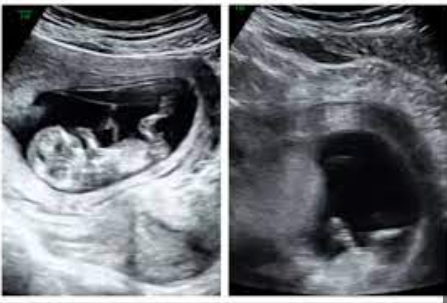

„Na monitoru jasno vidim tri fetusa. Čestitam – nosite trojke!“

U trenutku, soba se zavrtjela. Marina je gledala ekran, pokušavajući razaznati oblike koji su se kretali u crno-bijelim sjenama. Trojke. Tri srca. Tri života. Tihi šok ispunio je prostor, a onda su krenule suze – suze nevjerice, straha, ali i neobjašnjive radosti.